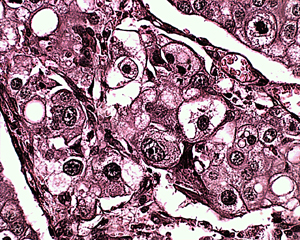

Гистологическое исследование представляет собой исследование тканей под микроскопом с целью проведения морфологической оценки патологических тканей. Исследование необходимо проводить во всех случаях, когда речь идет о постановке диагноза при выявлении опухолевых процессов или эррозивно - язвенных процессов любой этиологии. Кроме того это исследование позволяет провести уточняющую постановку посмертного диагноза в случае гибели животного.